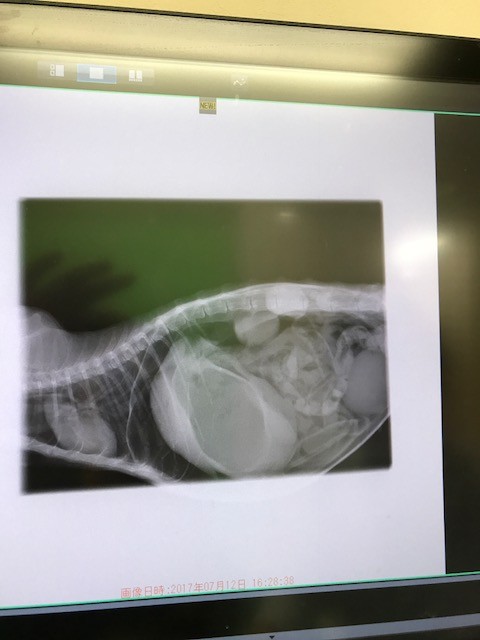

お腹にはガスがパンパンに溜まって居ます

腎臓も ほとんど機能して居ないそうですが 、

何とか手術を乗り越えて貰いたいです。

夜遅くまで 手術をして下さった 先生方に 感謝しか有りません。